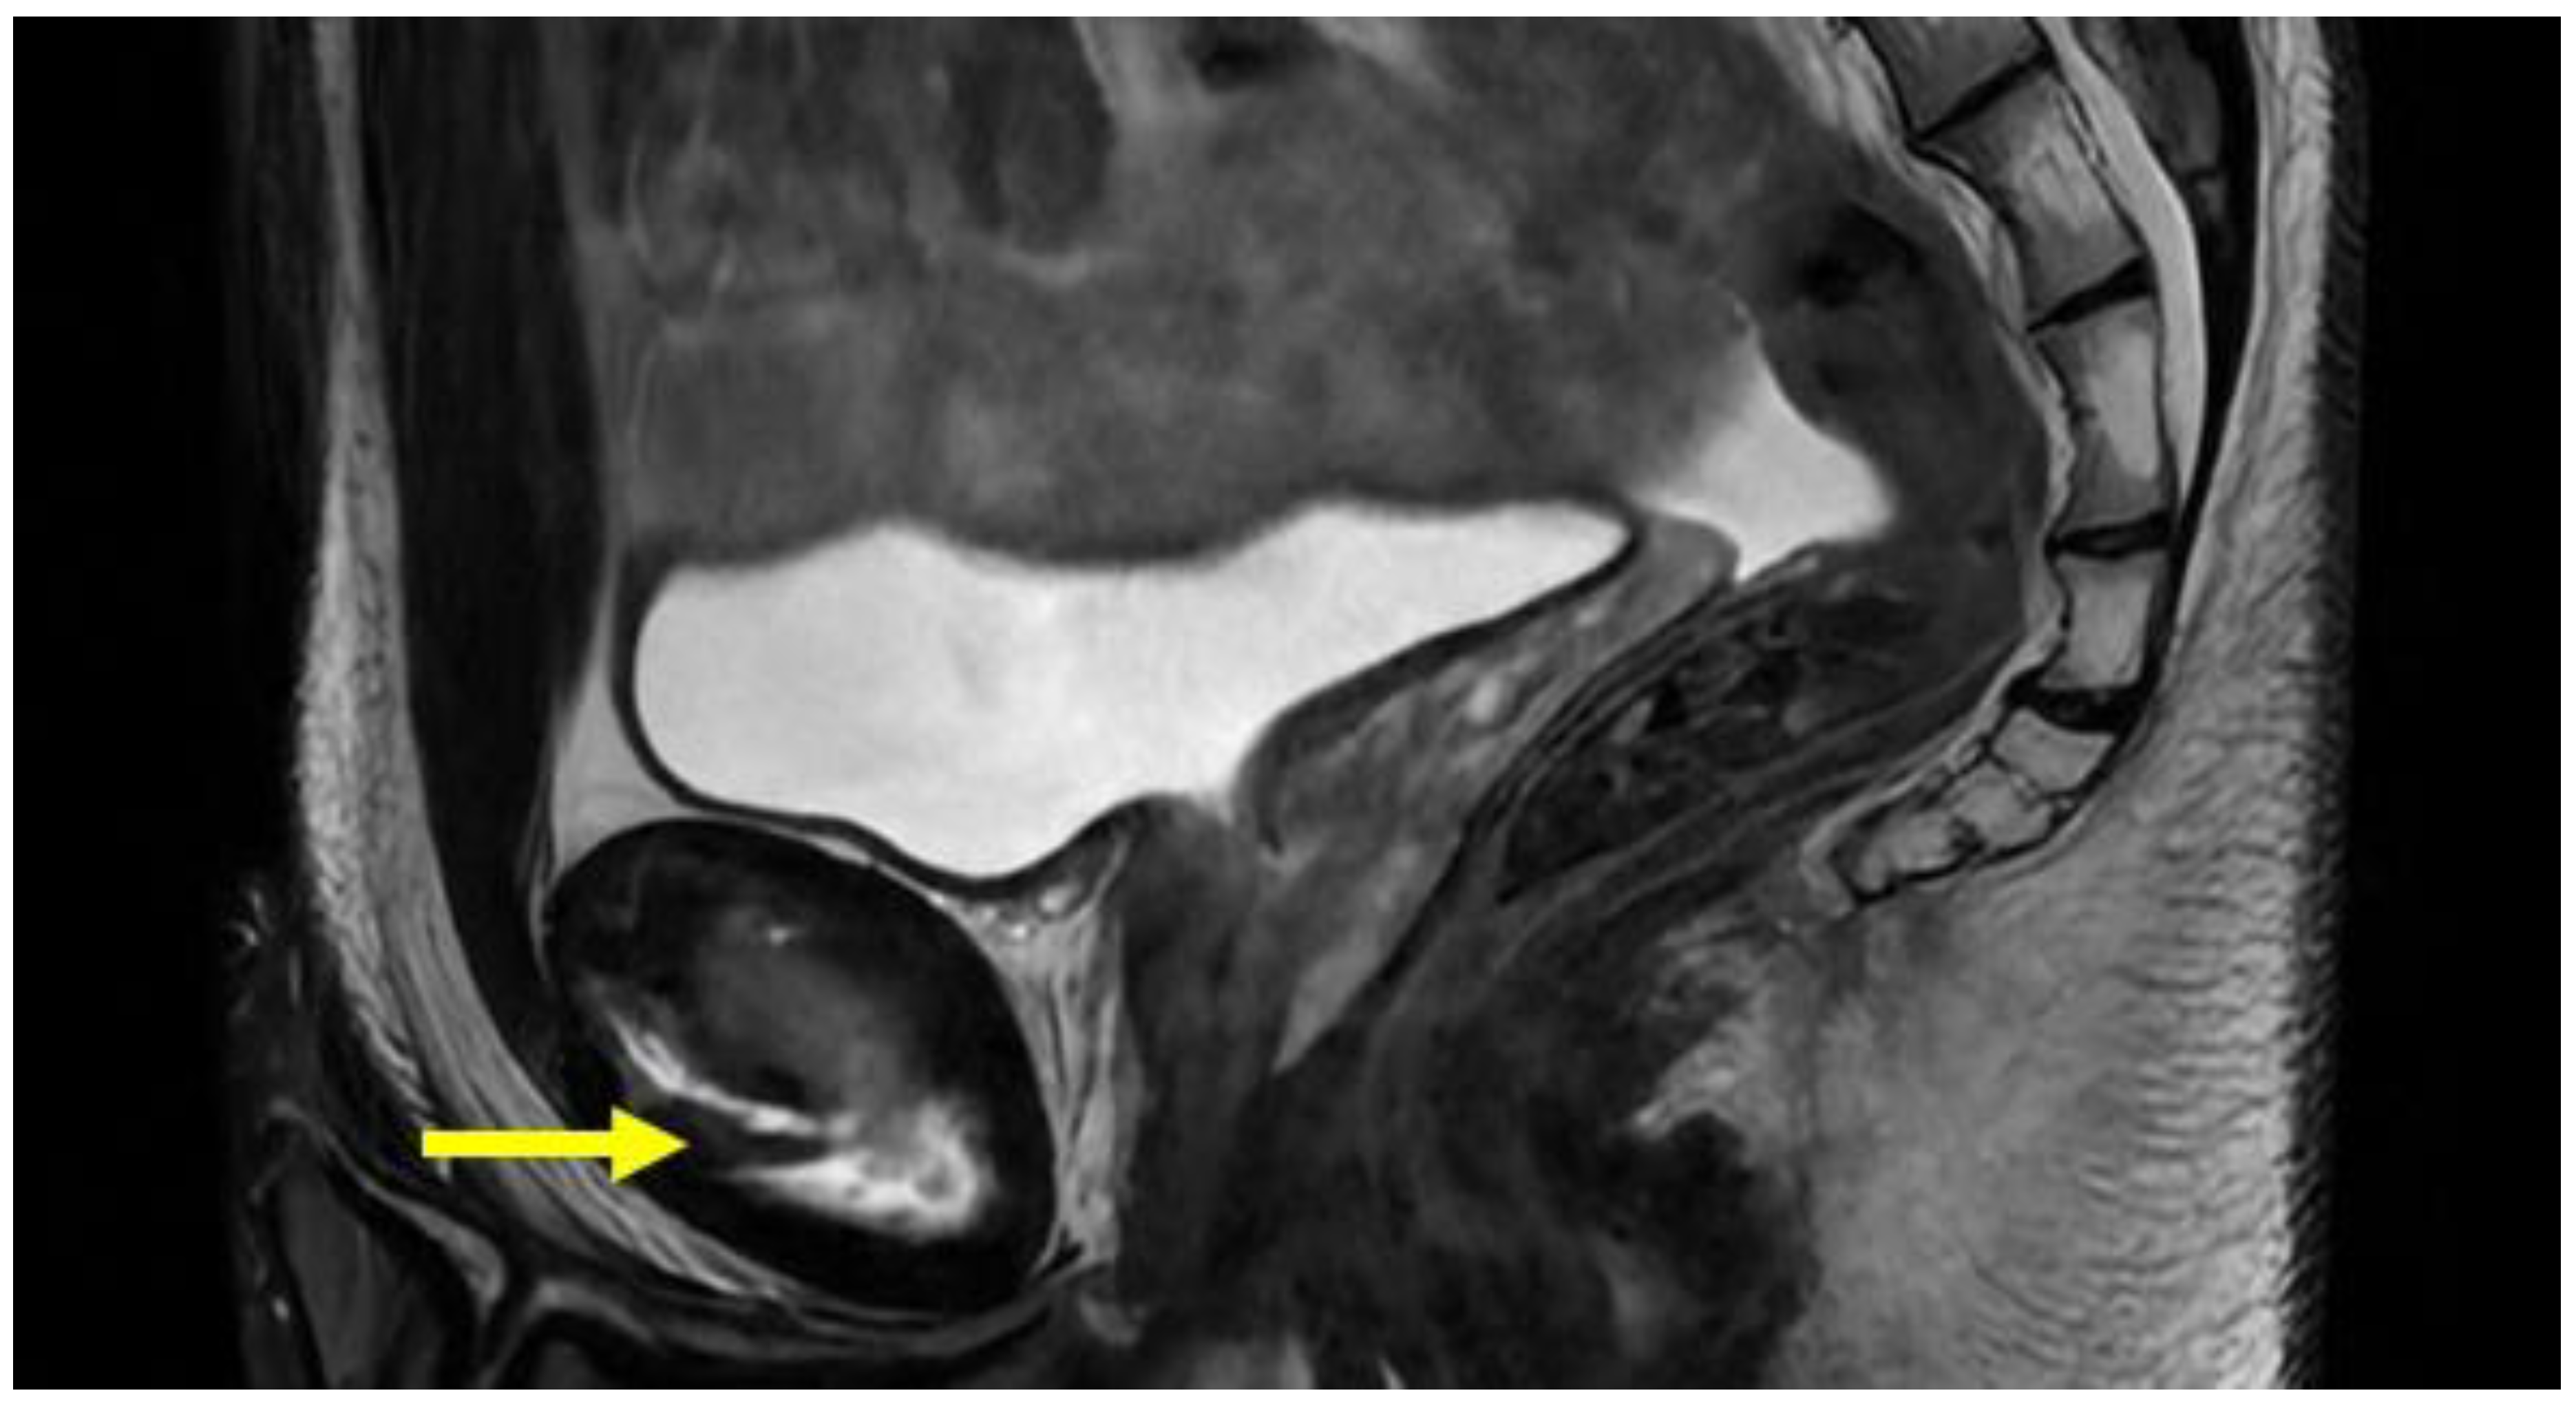

| Central disc protrusion | Coronal T1. Axial oblique T1 | Protrusion of the central symphyseal fibrous disc. In coronal images, the central disc protrudes cranially with respect to the margins of the symphyseal joint. In oblique axial sequences, it protrudes posteriorly. |